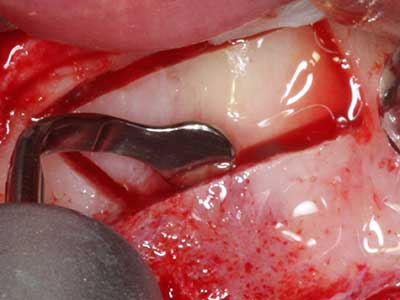

Piezosurgery has additional advantages when harvesting bone blocks. In addition to the high precision with osteotomy described above, the use of the thin saw tips specifically minimizes loss of material. Greater loss of material during harvesting can be expected with the thicker instrument tips, particularly when using Lindemann drills (Lakshmiganthan, Gokulanathan et al. 2012). The basal separation, which is necessary particularly for retromolar block transplants, is simplified by specially designed rectangular saws, with the result that piezosurgery is viewed as a precise, simple and safe procedure for harvesting retromolar bone blocks (Happe 2007) (Fig. 1-12).

When surgical procedures are performed on bone in the immediate vicinity of sensitive structures such as blood vessels or nerves, rotary instruments pose a significant risk of iatrogenic injury. Piezoelectric devices can be helpful for preparation of bone covers and removal of hard tissue close to nerves, particularly for exposure of nerves after iatrogenic injury but also during nerve lateralization for resective and reconstructive procedures or implant placement (Fig. 17-20). Light contact between the piezotip and the nerve does not generally result in damage but proceeding incautiously with saw-like motions or attachments where a residual bone substrate remains may cause temporary or even permanent nerve damage. However, the risk of damage is considered to be substantially lower than when using saws or milling instruments (Pereira, Gealh et al. 2014).